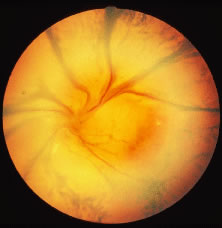

A variable number of eyes, up to 75%, develop retinal detachments (Fig. 5). Prophylactic laser for demarcating the areas of active retinitis from normal retina has been advocated to create chorioretinal adhesions that prevent retinal detachments around sites of retinal break formation (which usually occur at the zone between affected and healthy retina). Han and associates43 reported five cases treated with prophylactic laserpexy in addition to antiviral, steroid, and antiplatelet therapy. After 15 months of follow-up, no retinal detachments were noted. Sternberg and coworkers44 described a 75% decrease in the rate of retinal detachment using prophylactic photocoagulation. Some have advocated the creation of a “new ora serrata” by applying confluent rows of laser burns posterior to the areas of retinitis. However, if traction forces from vitreous organization, epiretinal membrane (ERM) formation, or proliferative vitreoretinopathy develop as they commonly do, the contractile forces will be able to overcome any increased chorioretinal adhesion created by the laserpexy. However, McDonald and associates45 reported failure of prophylactic peripheral laserpexy to prevent retinal detachment in ARN patients. In addition, many cases of ARN result in a severe vitritis, limiting the view for a planned laserpexy (Fig. 6). Therefore, vitrectomy with endolaser and concomitant encircling of the eye with a scleral buckle to reduce traction may be required in some patients.46,47 Decisions relating to the need for scleral buckling to support retinal breaks and the use of silicone oil or long-acting gases to repair retinal detachments should be made by an experienced vitreoretinal surgeon.40,48 Selection of cases to undergo operation should be made with consideration given to optic nerve function, visual potential, and medical control of retinitis.

The ocular complications of ARN are myriad. During the active infection, uveitis is a prominent feature. Secondary glaucoma may develop because of inflammatory debris in the trabecular meshwork. Posterior synechiae may form with resulting pupillary block and occlusion of the angle by forward movement of the peripheral iris. Pupillary membranes and cataract development have been described. Optic nerve atrophy has been noted and may be due to loss of ganglion cell bodies in the retina or direct invasion of the nerve head by the virus with subsequent inflammation and swelling. Iris neovascularization and neovascular glaucoma may occur. Disc and retinal neovascularization with subsequent vitreous hemorrhage have also been noted.16,49 Finally, a blind painful eye may develop, necessitating retrobulbar alcohol injection or enucleation.